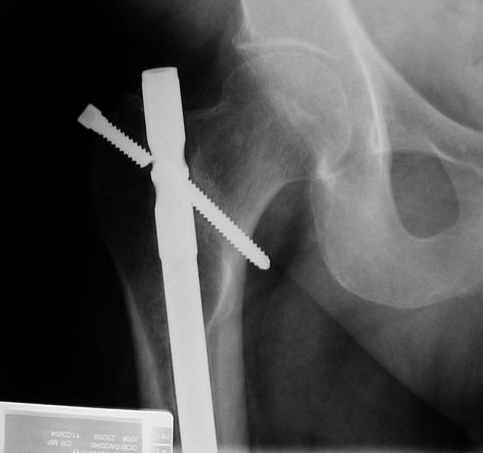

X-ray is of proximal locking screw failure in a 50 male with diaphyseal nonunion.

I would appreciate suggestions for deaaling with this. With the screw broken near the lateral edge it concerns me that trying to pull the nail out might fx the neck. I would like to do an exchange nailing for the diaphyseal nonunion. Thanks for your thoughts.